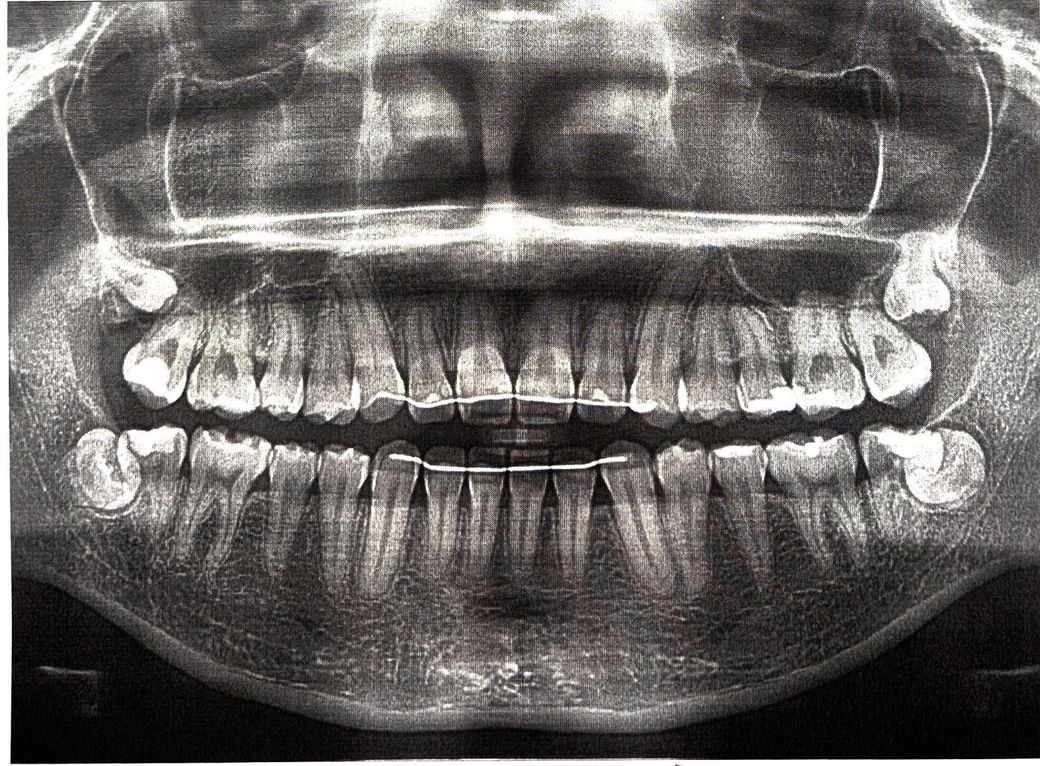

xray 상으로 봤을 때 충치가 있나요? 그리고 잇몸이 좀 내려간 거 같은데 그것도 봐주시면 감사하겠습니다.

사진이 흐립니다만 2차 우식을 의심해볼 수 있을 것 같습니다. 진단은 더 좋은 화질의 자료가 필요합니다.

엑스레이 상으로는 큰 충치가 잇어 보이진 않고 잇몸상태도 나쁘진 않으니 지금처럼 관리를 하시면될것같습니다.

잇몸뼈는 어디가 내려가있진 않고 정상적이기 때문에 걱정은 하지 않으셔도 되겠습니다. 충치는 왼쪽 위 어금니가 약간 애매하긴 한데 조그만 사진을 찍어봐야 더 정확히 알 수 있을 것 같습니다.

파노라마 사진으로는 충치 감별이 어려울 수 있습니다. 충치가 의심되는 치아는 사진상 오른쪽 위 첫번째 큰 어금니, 왼쪽 아래 첫번째 큰 어금니 입니다.

엑스레이 사진으로는 잇몸이 아니라 잇몸뼈가 내려갔는지를 봅니다. 잇몸뼈가 특별히 나이에 비해 낮거나 그러진 않습니다.